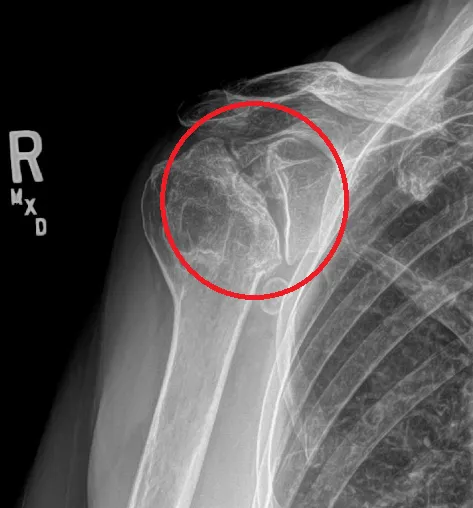

肩關節退化 由肩胛骨與鎖骨、肱骨所組成的肩關節之銜接處沒有達到正確的排列位置,進而導致此關節所負責之動作方向長年導致磨損或增生骨刺逐漸產生角度產生受限、週邊肌肉神經筋膜等軟組織產生發炎、鈣化、不適症狀,即為肩關節退化。

整個肩關節在動作上所需的,任何一處軟骨磨損進而讓骨骼拉扯肌肉及韌帶的地方,都能造成關節退化的症狀出現。 但是並非要直接影響到肩關節,有些也能因為影響到包覆關節的筋膜,而造成近似關節退化的症狀出現,進一步的使關節無法正常運作而有痛或無力緊繃等感覺。

X光檢查以及常見該肌肉力量、動作功能、症狀主述判斷